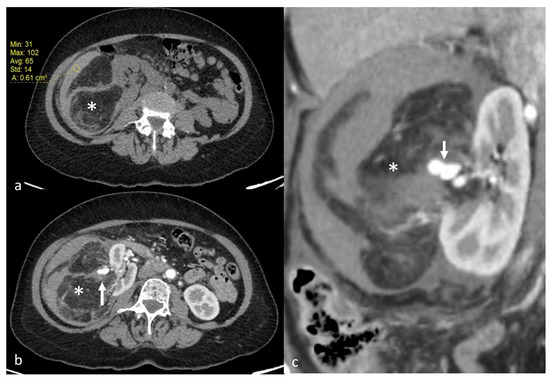

Figure 6.

Postembolization lipuria in a 70-year-old patient with a right AML. (a) Intratumoral necrosis (*) on axial computed tomography with injection and urinary acquisition (b) Fat-supernatant indicating lipuria (white arrow) on axial computed tomography with injection and urinary acquisition (c) Intra-ureteral fat (white arrows) on coronal computed tomography with injection and urinary acquisition.

Minor complications were recorded in three patients (12%) and major complications in two patients (8%). One patient had a non-targeted embolization of the renal parenchyma during embolization (minor complication). The Onyx was not correctly visible (on poor homogenization with tantalum powder). The non-target embolization represented 28% of renal parenchyma, with no alteration of renal function at follow-up. One other patient had a pseudoaneurysm of the punctured femoral artery resulting in an additional day of hospitalization (minor complication). Doppler follow-up showed the resolution of the latter after being successfully treated by ultrasound-guided compression and monitoring. One patient had a post-embolization syndrome (PES) 48 h after embolization, with further anti-inflammatory and analgesic treatment (minor complication). One patient had a renal artery dissection during embolization, ultimately leading to non-target embolization of 20% of the kidney (major complication). The patient then had a pulmonary embolism and the appearance of a bilateral pleural effusion. She presented with hypovolemic shock due to a massive retroperitoneal rupture of the tumor. She also developed healthcare-associated pyelonephritis (major complication). One other patient presented, 15 days after embolization, a superinfection of the embolization site with fistulization in the pyelocaliceal system, leading to lipuria (Figure 6). The patient was hospitalized with antibiotics and analgesics (major complication). The AML drained itself almost completely into the pyelocaliceal cavities, conducting a volume shrinkage of 99%.